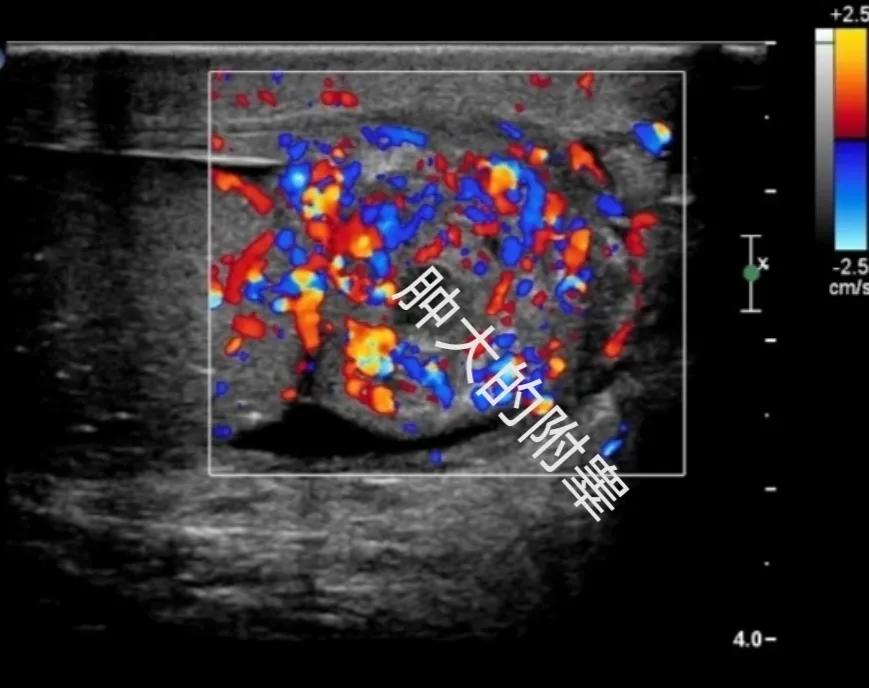

而超声检查也是最常用的检查手段,超声一般会发现附睾,尤其是附睾尾部,肿大,回声不均,血流信号丰富,触痛非常明显,有时候超声仪器的探头设备一碰,患者就疼得受不了,阴囊肿胀很明显的阴囊的*丸睾**鞘膜腔内可见到积液,这也是咱们有时候从外表看起来阴囊明显肿大的原因,附睾炎症比较严重的时候还会累及到*丸睾**和精索区,从而导致*丸睾**炎症,表现为*丸睾**肿大、血流信号丰富,精索炎症,表现为精索区域精索组织肿胀、回声增强、血流信号丰富。接诊的时候询问病史过程中发现一个共同的问题,只要是患者一摸到有东西,他们就非常害怕,其实通过上面介绍,摸到的疙瘩就是肿大的附睾,一些症状比较轻的患者刚开始其实就是疼,但这个时候好多男性同志们都不来检查,觉得可能就是有点不舒服,过两天就好了,结果等了两天,不仅没好,反而疼得越厉害了,自己一摸还摸到了疙瘩,结果心里就犯嘀咕了,有点担心了,才来医院检查,这样其实反而耽误了治疗。

肿大的附睾,伴有丰富的血流信号